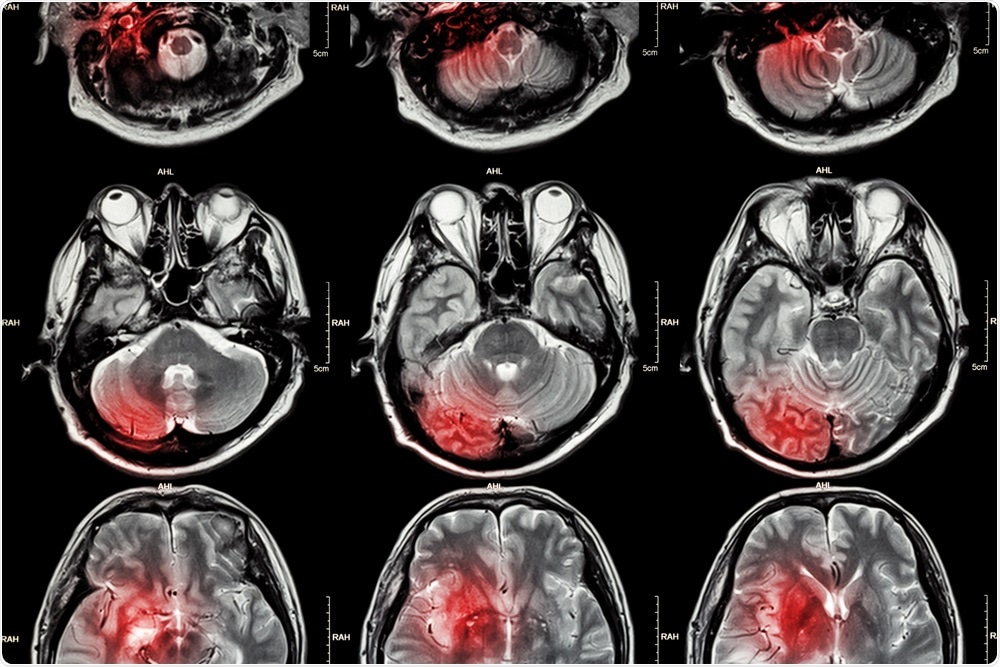

MRI of the brainPuwadol Jaturawutthicha | Shutterstock